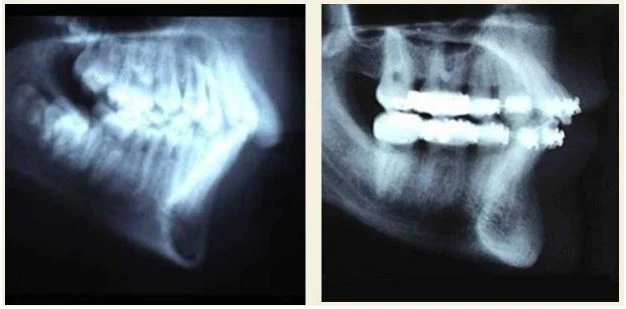

- Di xa răng cối: Để giải quyết chen chúc mà không phải đưa răng cửa ra trước. Ở cung dưới, việc di xa răng cối được tiến hành từ bộ răng hỗn hợp. Di xa răng cối ở cung dưới sẽ bị ngăn cản do R7 và R8, hoặc là do sự giới hạn của cành lên xương hàm dưới.